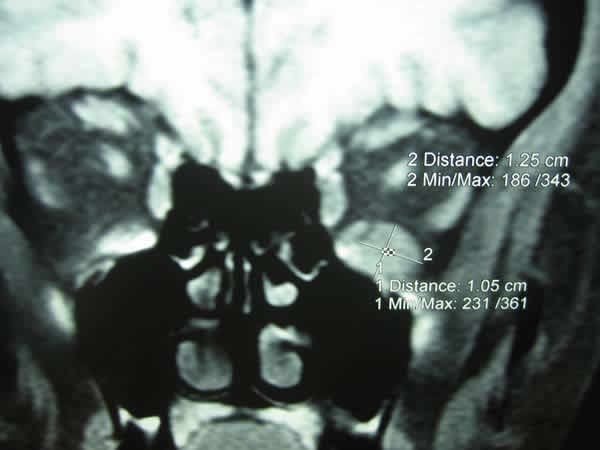

Aporta un estudio de resonancia magnética nuclear (RMN) de órbitas con administración de Gadolinio en cortes axial, coronal y sagital en el que se aprecia una tumoración que expande el tercio central del músculo recto inferior, con diámetros craneocaudal, anteroposterior y lateromedial de 1,5x2x1 cm, que se realza con contraste de forma irregular (figs. 1 y 2).

Fig. 2: RMN coronal SE T1 supresión grasa con gadolinio (Gd-DPTA), objetivándose tumoración en el músculo recto inferior, con diámetros craneocaudal, anteroposterior y lateromedial de 1,5x2x1cm, que se realza con contraste de forma irregular.